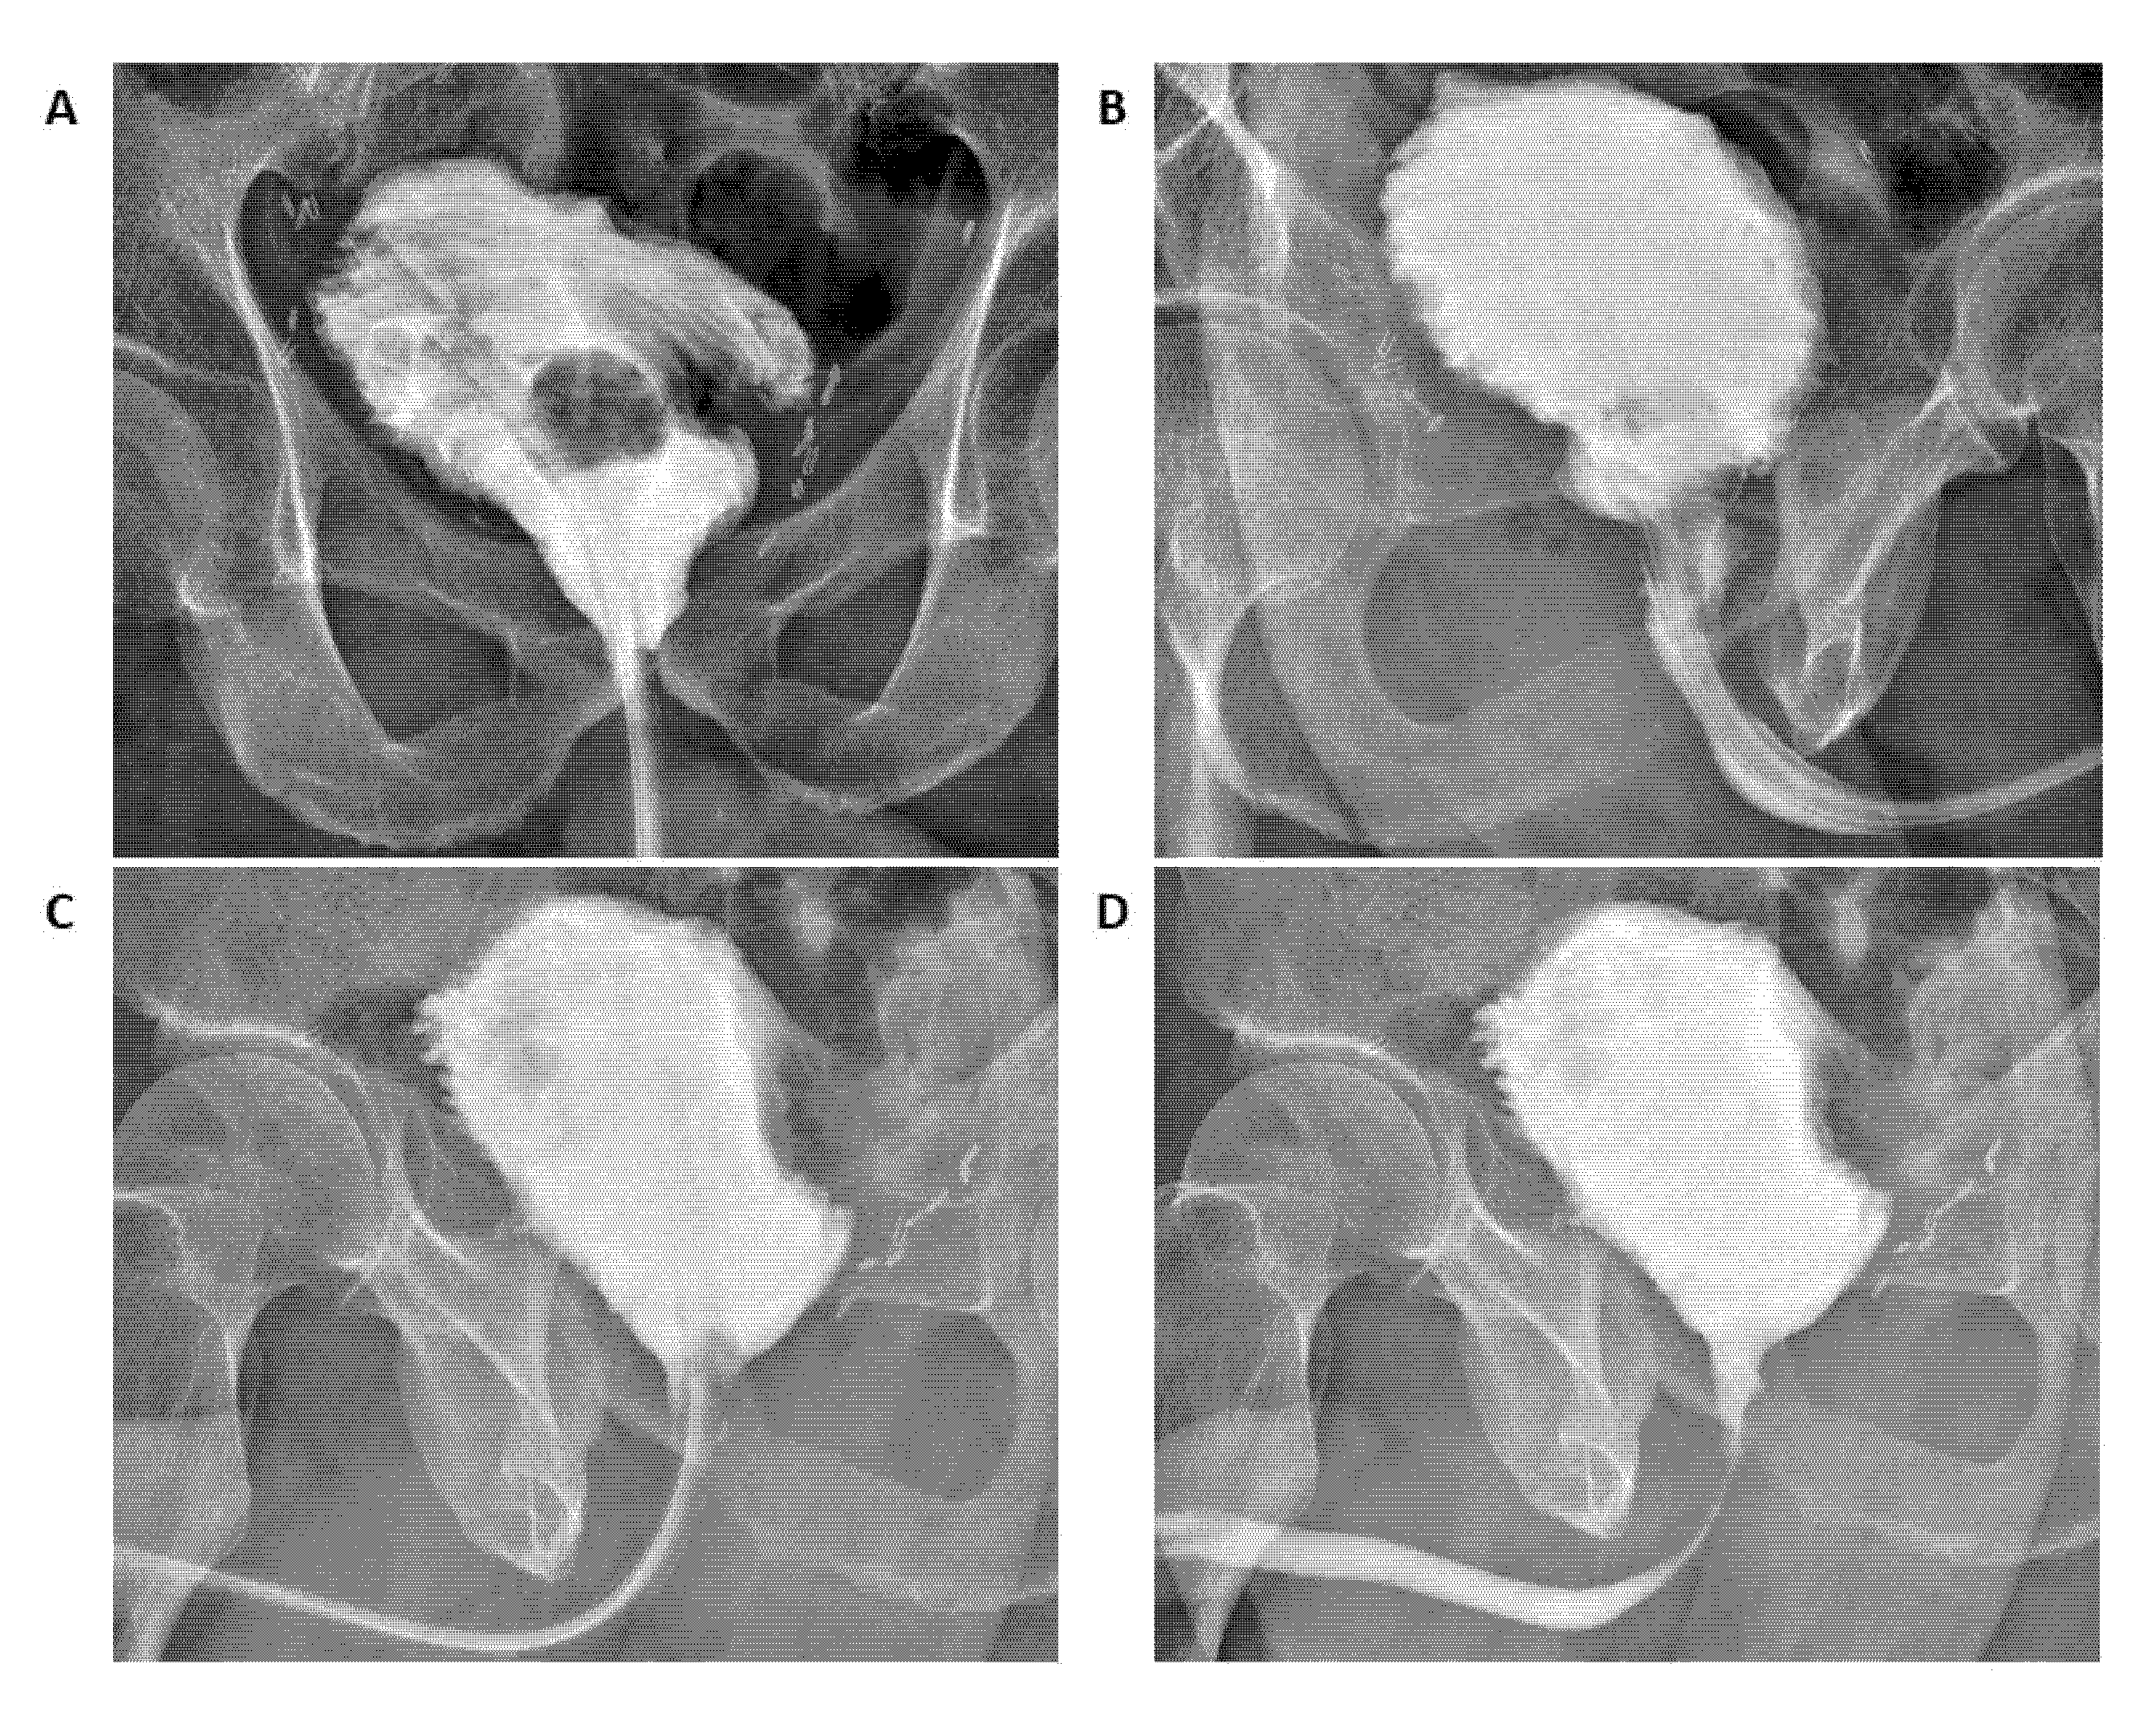

2.2. Description of the Surgical Technique